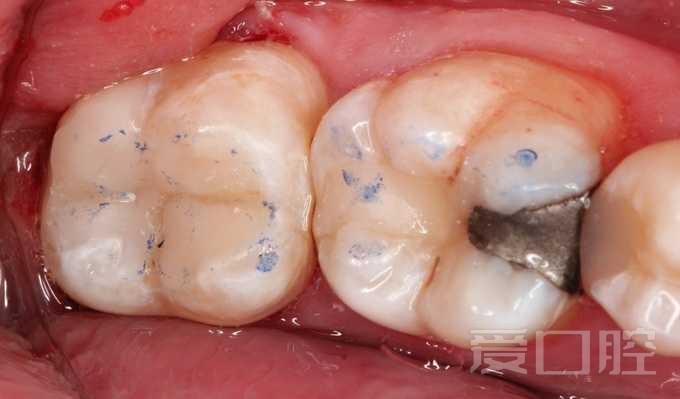

一个比较困难的补牙病例

by Adrian Chen